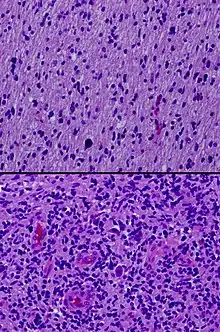

In pathology, grading is a measure of the cell appearance in tumors and other neoplasms. Some pathology grading systems apply only to malignant neoplasms (cancer); others apply also to benign neoplasms. The neoplastic grading is a measure of cell anaplasia (reversion of differentiation) in the sampled tumor and is based on the resemblance of the tumor to the tissue of origin.[1] Grading in cancer is distinguished from staging, which is a measure of the extent to which the cancer has spread.

Pathology grading systems classify the microscopic cell appearance abnormality and deviations in their rate of growth with the goal of predicting developments at tissue level (see also the 4 major histological changes in dysplasia).

Cancer is a disorder of cell life cycle alteration that leads (non-trivially) to excessive cell proliferation rates, typically longer cell lifespans and poor differentiation. The grade score (numerical: G1 up to G4) increases with the lack of cellular differentiation - it reflects how much the tumor cells differ from the cells of the normal tissue they have originated from (see 'Categories' below). Tumors may be graded on four-tier, three-tier, or two-tier scales, depending on the institution and the tumor type.

The histologic tumor grade score along with the metastatic (whole-body-level cancer-spread) staging are used to evaluate each specific cancer patient, develop their individual treatment strategy and to predict their prognosis. A cancer that is very poorly differentiated is called anaplastic.